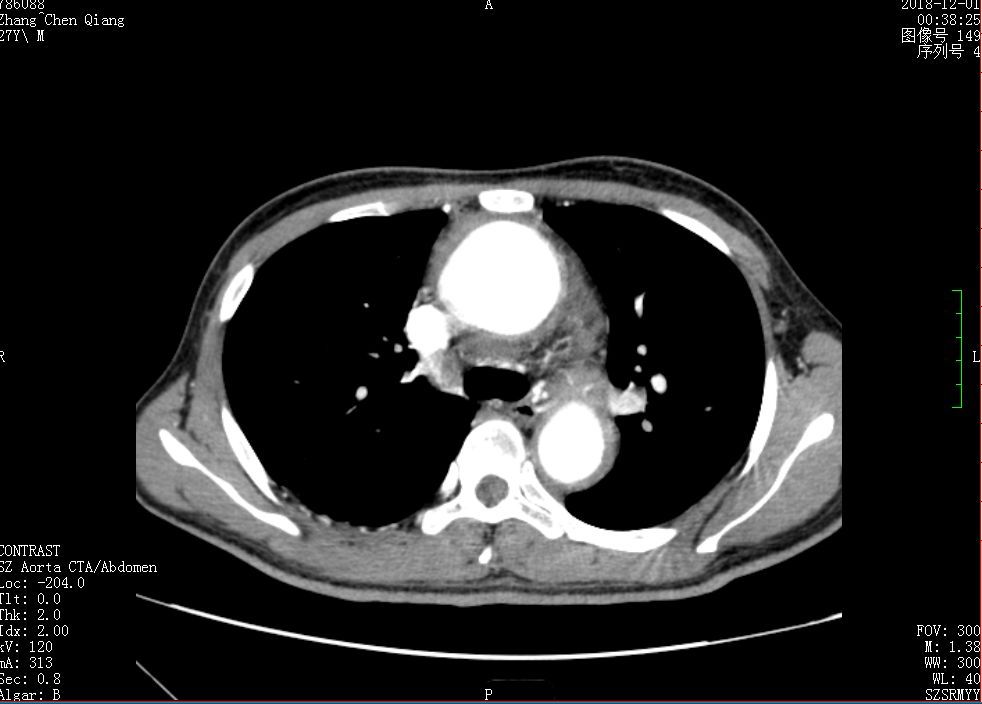

27岁的张先生(化名)胸背部疼痛一个多月了,本以为只是简单的疼痛,没想到越来越严重,还伴有咯血。

仅在深圳市人民医院完善术前常规检查期间,张先生就咯血300ml左右。

经检查,发现张先生是降主动脉穿透性溃疡!这是一种潜在风险大的疾病,大的溃疡可能迅速发展成为夹层、大动脉破裂,出现失血性休克、重要脏器缺血等危重情况。

完善术前准备后,2018年12月6日9:40,深圳市人民医院心外科主任郑齐军团队为张先生实施了插管麻醉下行升主动脉替换+全主动脉弓置换术+降主动脉覆膜支架置入术。